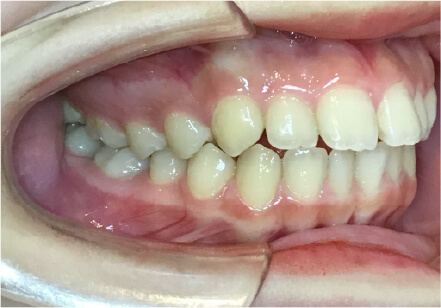

過蓋咬合の症例

15歳

/

女性

相談内容

前歯と前歯が噛んでいない

カウンセリング・診断結果

過蓋咬合

治療内容・方法

全額アライナー矯正

術後の経過・現在の様子

クリアライナー使用

治療のリスク

痛み・歯根吸収・歯肉退縮・虫歯・後戻り

費用・治療期間

830,000円、2年

トレーニングなど